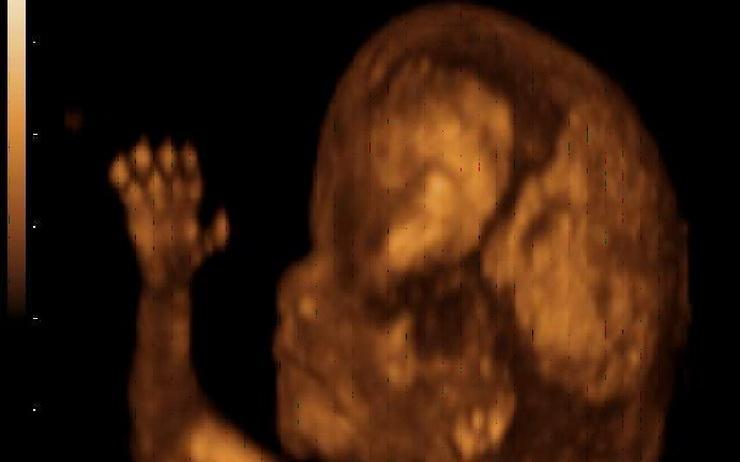

L’échographie 4D, qui regroupe aujourd’hui l’Etat de l’art de la technologie, est développée en ajoutant l'élément de mouvement aux images échographiques 3D fixes, ce qui permet la visualisation du fœtus et de son mouvement dans l'utérus.

--> Ce lien entre une mère et son enfant que créé l'échographie est un moment divertissant et profitable car la femme enceinte a la chance de voir son bébé et ses mouvements pendant l’examen.